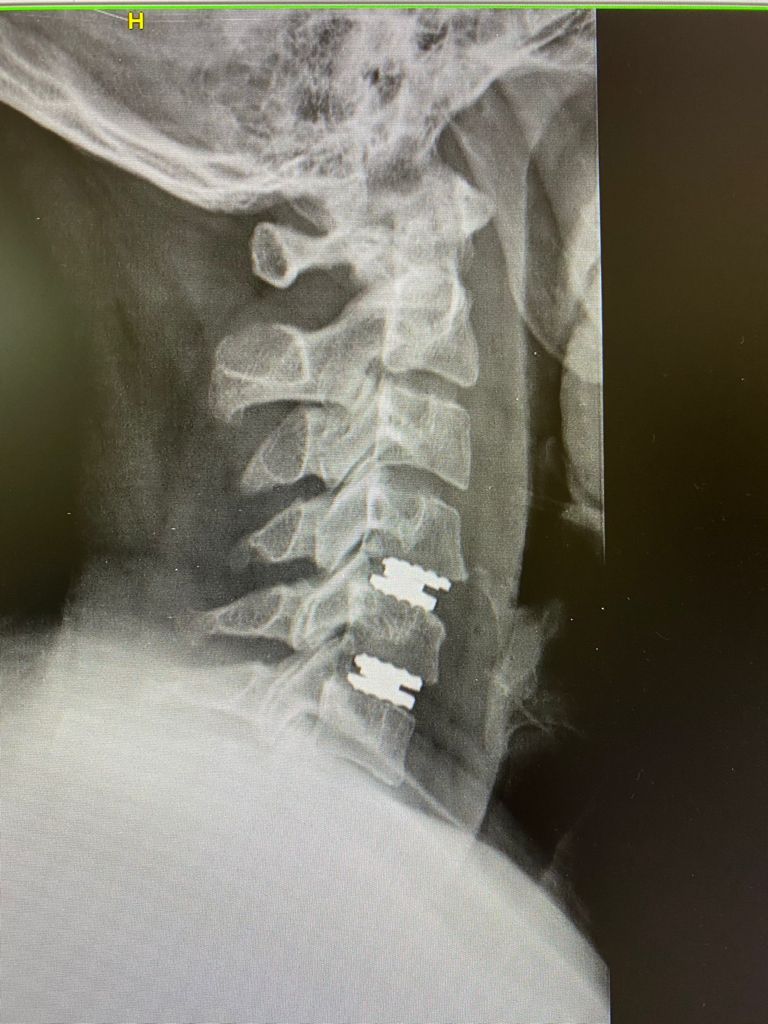

Fotos y videos

Estimulación magnética transcraneal para el tratamiento de ansiedad y depresión por la pandemia así como deterioro cognitivo

04/01/2022